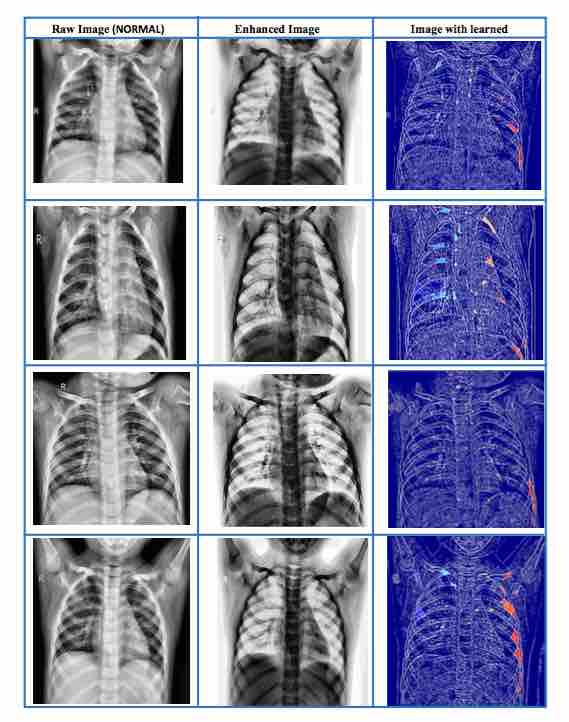

Image processing techniques enhance the targeted X-ray images and use an algorithm to create visual cues related to each particular disease.

“A tailor-made AI algorithm scans enhanced images and then extracts visual cues to help automatically identify coronavirus cases and monitor the development of the virus in infected people,” said Professor Abdul Sadka.

It uses multiple layers of information processing to automatically build a picture of what to look for in X-rays, then trains a deep learning model to classify the type of the disease.